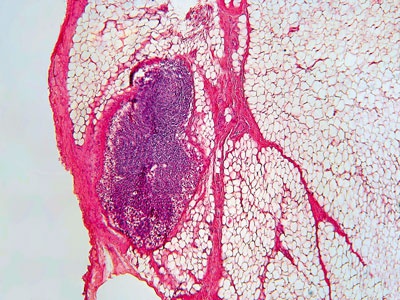

Рис. 26. Стократное увеличение околощитовидной железы

Так, паратгормон синтезируется в околощитовидных железах и совместно с кальцитонином и витамином D регулирует содержание кальция в организме. Главнаяй же функция этого гормона заключается в обеспечении постоянного количества ионизированного кальция в крови. Осуществляется это путем вымывания кальция из костей, а также путем усиленного всасывания его в кишечнике и почках. Механизм выделения паратгормона и изменения количества кальция работает по принципу обратной связи. Плюс ко всему гормон околощитовидной железы участвует в обмене фосфора и магния.